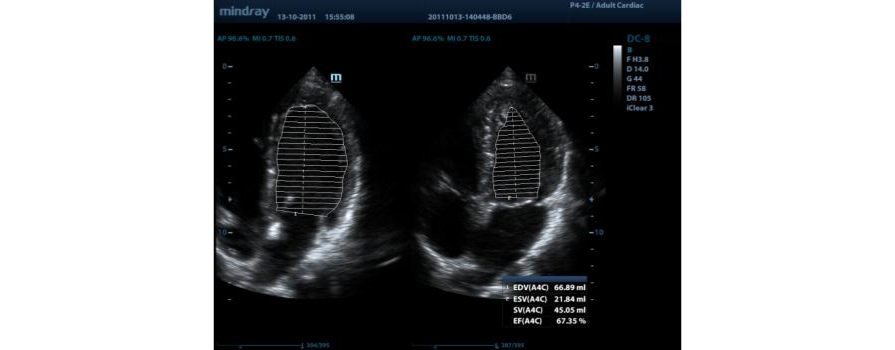

Auto EF (automatyczne wyliczanie frakcji wyrzutowej)

Jeden z inteligentnych sposob├│w analizy fragment├│w nagra┼ä, tzw. ?clip├│wŌĆØ echa 2D, aby mogli Pa┼ästwo automatycznie rozpozna? obrazy faz skurczu/rozkurczu oraz automatycznie wyliczy? parametry i frakcje wyrzutow? EDV/ESV/EF przy u?yciu metody Simpsona.

Auto LV (Automatyczny pomiar Obj?to?ci lewej komory serca)

Jest to prosta procedura pomiarowa dla lewej komory serca, wzmocniona przez funkcj? automatycznego obrysu i ?atw? korekt? r?czn?.